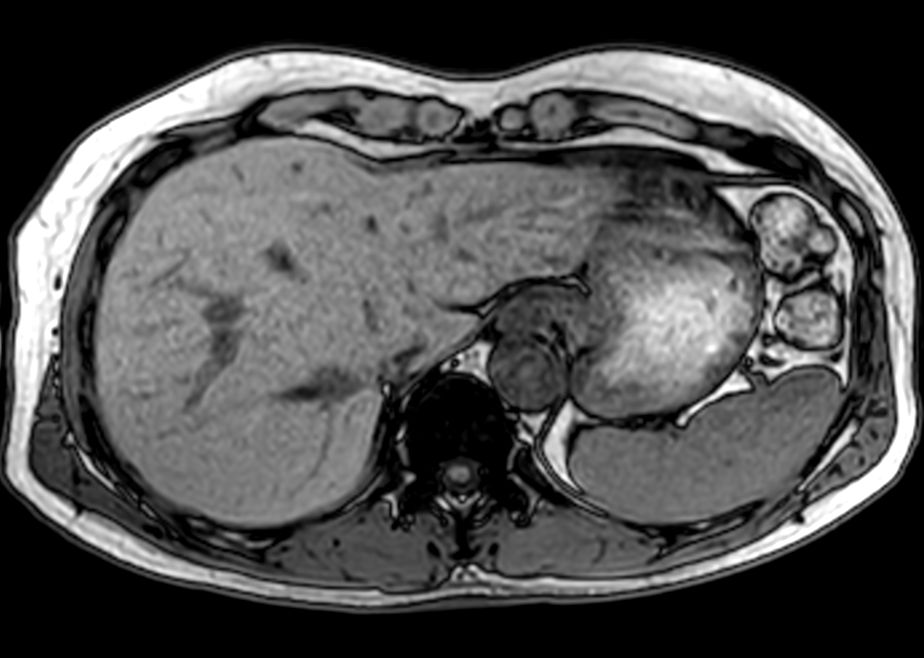

Coronal T1w FFE mDIXON (2 stations)Dual coil - Compressed SENSE